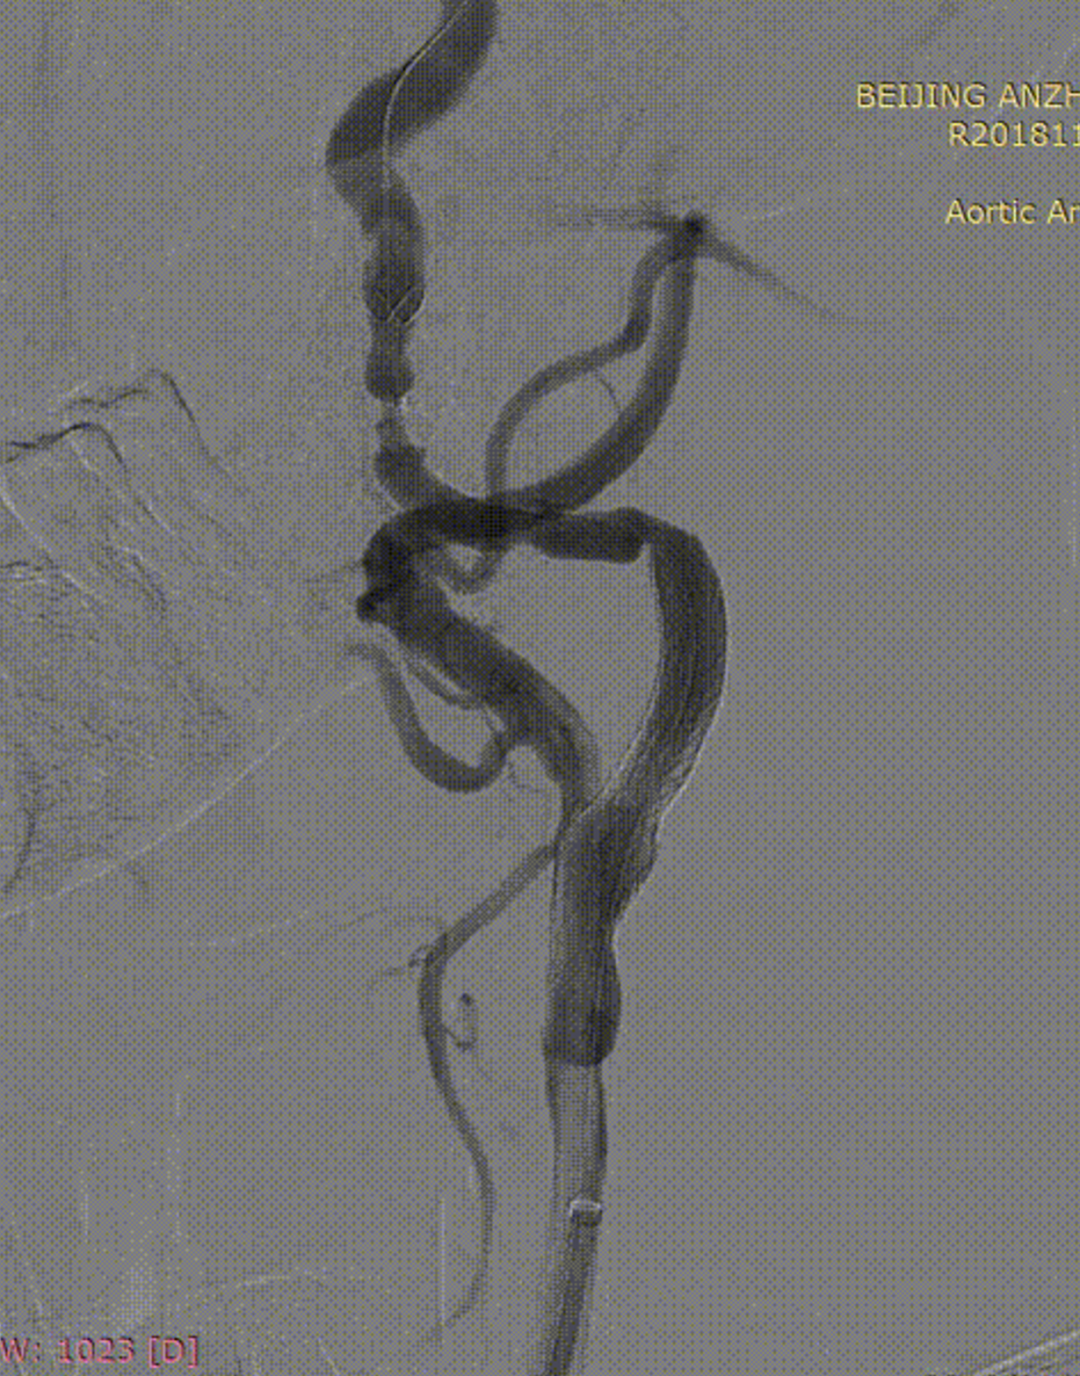

病例2:52岁男性,发作性胸痛2年,体检发现双侧颈动脉狭窄,冠脉情况严重,先行PCI,后行双侧CAS,先右后左,术后复查颈动脉支架通畅。

右侧术前

右侧术后

左侧术前

左侧术后